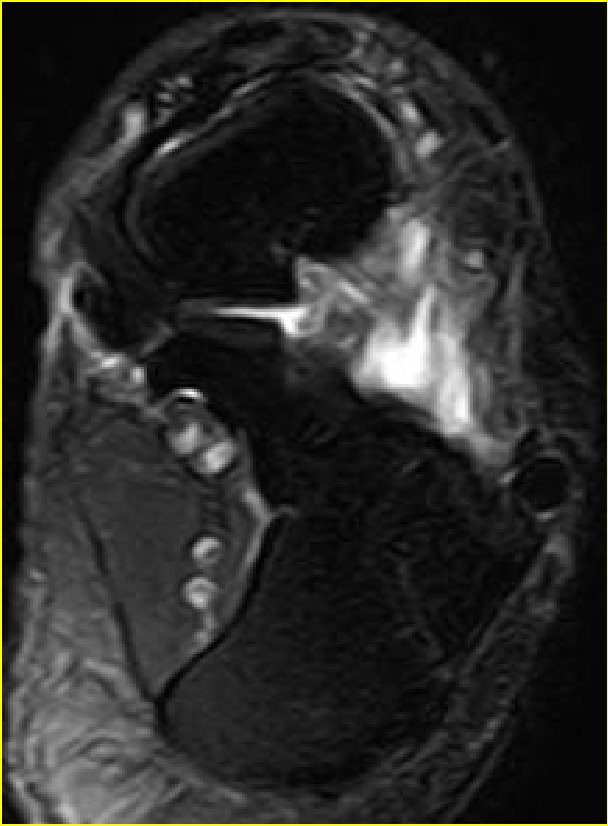

MR表现:(信号+形态)

• 正常跟腱呈均匀低信号

• 脂肪抑制T2WI图像上,跟腱内部或跟腱周围软组织出血或水肿表现为信号增高,跟腱断裂/撕裂表现为跟腱连续性中断或波浪状回缩

• 跟腱近端回缩,跟腱边缘磨损,呈螺旋状形态

• 撕裂处增粗的近端与远端之间可见疏松的连接